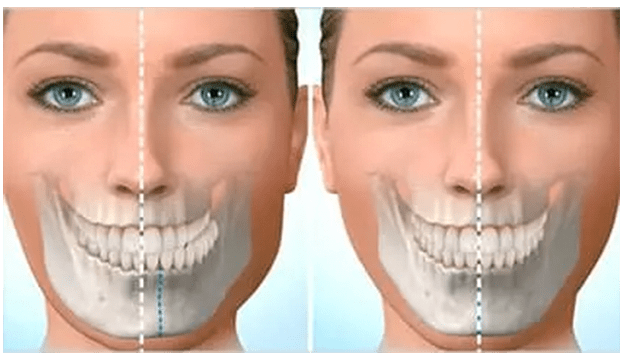

- Küçük çeneler ( micrognati ), underbite’ler (az ısırma) ,overbite’ler (örtülü kapanış) ve çapraz kapanışlar gibi yüz asimetrileri varlığında

Ortodontist ve çene cerrahı, tedavi planını geliştirmek için birlikte çalışır. Dişlerin ve çenelerin röntgenleri, resimleri ve modelleri, bu ameliyatın planlamasının bir parçasıdır. Bazen oklüzyonün (alt- üst dişler arasındaki kapanış) tam sağlanamadığı durumlarda ,ilgili dişlerde selektif mölleme ( aşındırma ) yada kaplama tedavisi uygulana bilinir.

- Alt ve orta yüzün daha dengeli görünümü